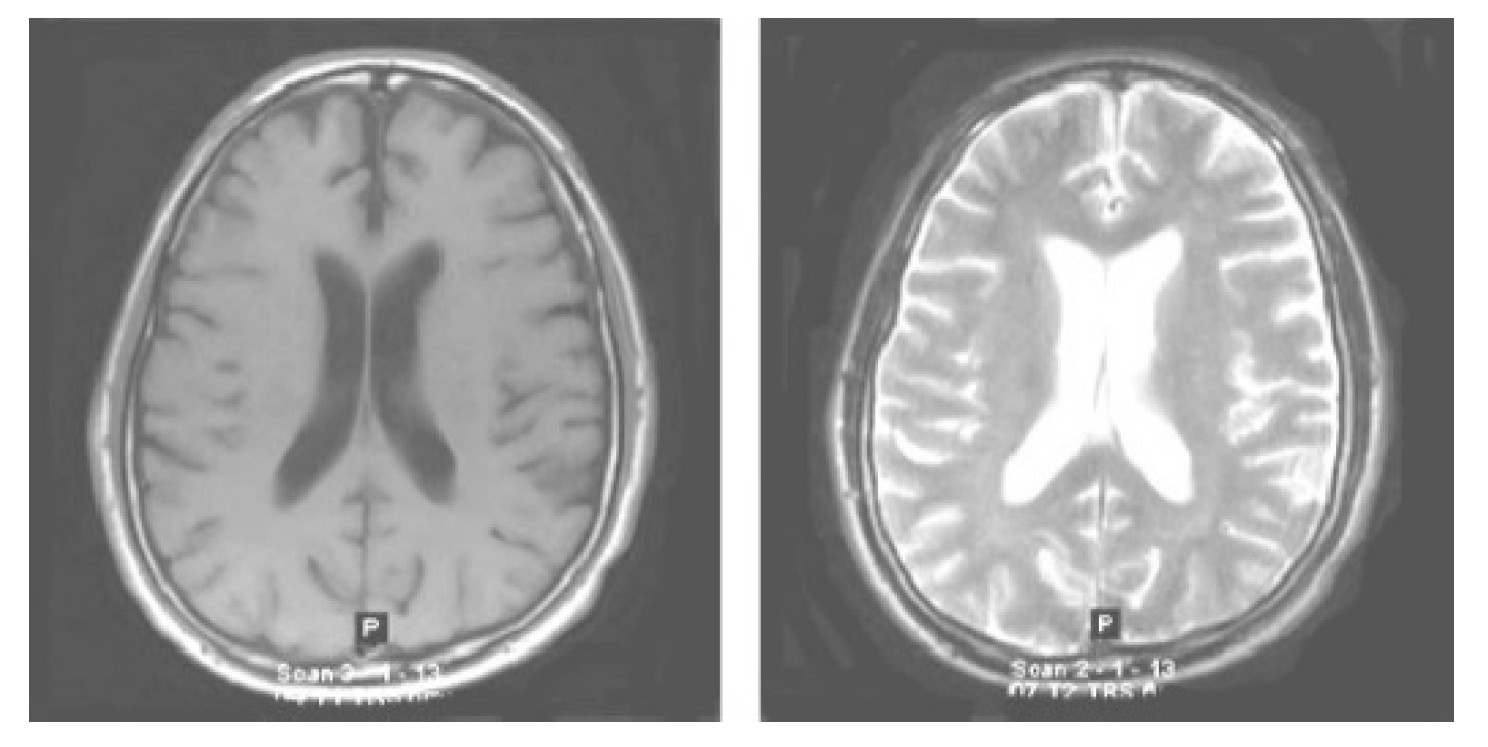

The very first stage of the suggested methodology is the acquisition of an image, in which an MRI image is used as an input for processing. In the application of the suggested methodology, brain tumor MRI images have been used. Four datasets containing T1-w and T2-w contrast-enhanced MRI images of three kinds of brain tumors were used. Images in the MRI format are stored in MATLAB R2021a, 255 × 255 in size, and they are shown as RGB images of grayscale as the ranges of their entries are from 0 to 1. Here, the black image is represented by 0 while the white image is represented by 1. Entries between 0 to 1 represent the variation in intensity from black to white (see Figure 2).

Figure 2.

Original normal brain T1-weighted and T2-weighted MRI images.